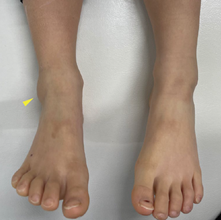

腓腹神経損傷

腓腹神経は足部外側に走行しており、足関節の捻挫で伸長されて損傷するリスクがあります。二分靱帯周囲で腓腹神経に沿った圧痛やTinelʼs sign が陽性で、圧痛部位より足先に向かって知覚鈍麻を認める点が鑑別のポイントです。

青い部分に感覚鈍麻を認めます。Tinel‘ssignは、打腱器でたたくとビーンと響く神経の痛みを訴えるサインのことです。

診察において

直接的な視診(腫れ、血種、変形の有無)と触診(熱感、疼痛場所、可動性の確認)が大切です。視診では腫脹と皮下出血の有無を確認します。捻挫に伴う靱帯損傷は重症であるほど腫脹が強くなります。外側靱帯損傷の場合は靱帯よりも遠位の踵骨部分に皮下出血が認められることが多く、前下脛腓靱帯損傷では同靱帯直上の足関節前方外側部分に腫脹を認めます。